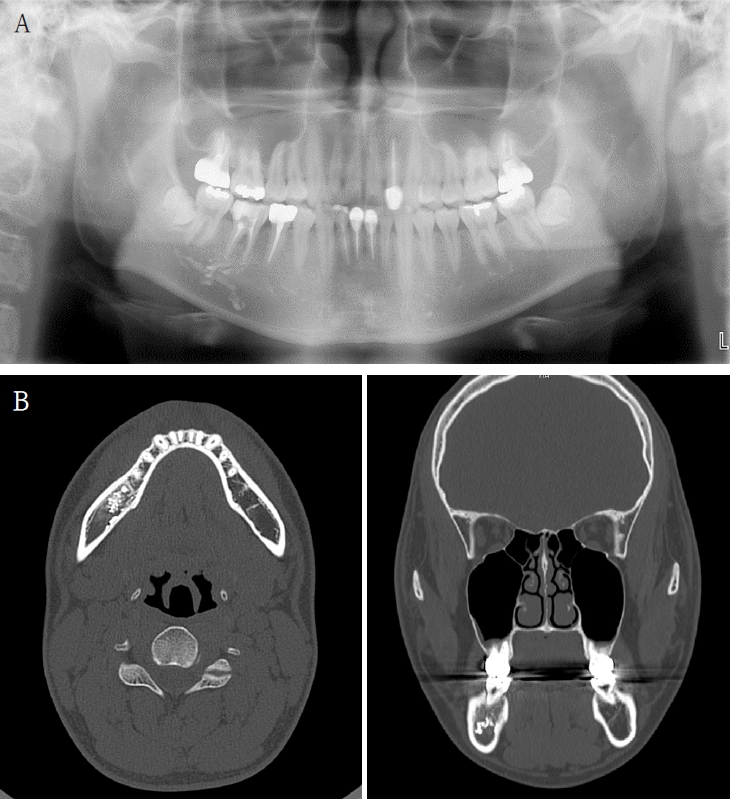

A 61-year-old female presented with intermittent right mandibular swelling and pain after root canal therapy was done using EndoSeal MTA 5 months ago. A panoramic radiograph, CBCT and bone scan confirmed material extrusion and mild localized bone changes (Fig. 4). Initial neurologic evaluation demonstrated nearly normal sensory function, with Visual Analog Scale (VAS) 4 discomfort. Surgical curettage was performed under local anesthesia. A post-operative panoramic radiograph confirmed the substantial removal of the foreign body (Fig. 5). Postoperatively, the patient reported significant improvement at both the one- and two-month follow-ups. Due to full symptom resolution, no follow-up neurosensory testing was performed.

A. Pre-op panoramic radiograph of Case 3 patient. B. Pre-op CBCT of Case 3 patient. C. Pre-op bone scan of Case 3 patient